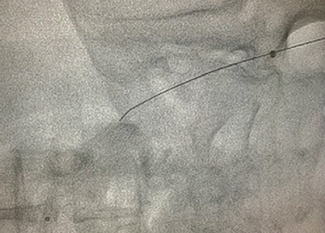

Pradnya Brijmohan Bhattad, MD; Luigi Pacifico, DO

A 54-year-old female presented with acute onset of typical substernal chest pain and was hemodynamically stable. A coronary angiogram (Figure 1/Videos 1-2, available on cathlabdigest.com) showed spontaneous coronary artery dissection (SCAD)...